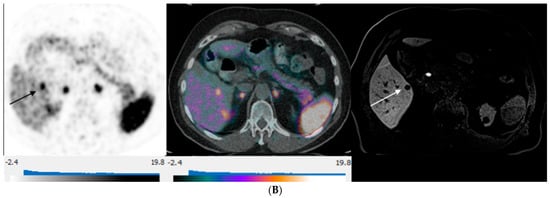

3. Results